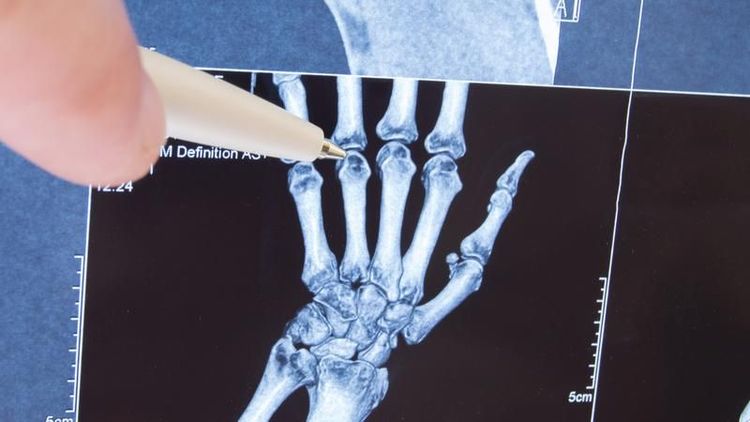

मंडळी, डॉनाल्ड उंगर यांनी ५० वर्षात डाव्या हातांची बोटे रोज २ वेळा मोडली. उजव्या हाताने जोर द्यायचा आणि डाव्या हाताची बोटे मोडायची हा त्यांचा रोजचा क्रम होता. त्यांनी स्वतः सांगितल्याप्रमाणे त्यांनी डाव्या हाताची बोटे तब्बल ३५,५०० वेळा मोडली. उजव्या हाताची बोटे ते फारच क्वचित मोडत. त्यांच्या स्वतःच्या शब्दात सांगायचं झालं तर ‘क्वचित किंवा उत्स्फूर्तपणे’.

तर, हे करण्यामागचं कारण होतं संधिवात खरंच होतो का हे पाहणं. बोटं मोडून झाली की ते स्वतःच्या हातांचं परीक्षण करायचे. शेवटी त्यांच्या लक्षात आलं की बोटं मोडल्याने संधिवात होतो ही फक्त एक अफवा आहे. ते यावर आणखी संशोधन करण्याच्या तयारीत आहेत. हे सगळं करत असताना त्यांना प्रश्न पडला की लहान मुलांना आणखी कोणकोणत्या खोट्या गोष्टी शिकवल्या जातात? कदाचित यावर पण ते संशोधन करतील.